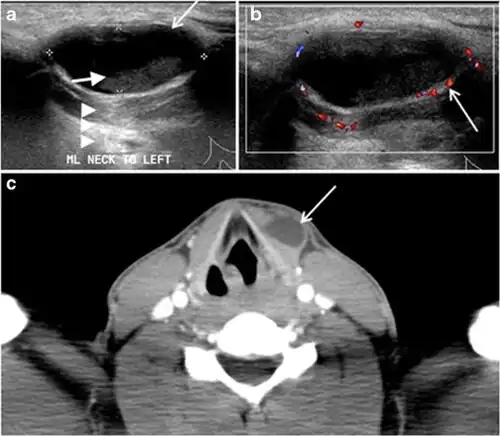

Fig. 19. Long-standing infected thyroglossal duct cyst in a 29-year-old male patient. a Transverse greyscale ultrasound at midline, just above the level of the thyroid gland, shows an oval cystic lesion with internal echoes (white arrows) and posterior enhancement (arrowheads). b Transverse colour Doppler ultrasound shows surrounding peripheral flow (white arrow). c Axial enhanced neck CT scan at the level of the thyroid cartilage demonstrates a slightly off-midline, well-defined, homogeneous cystic lesion embedded in the left strap muscle with peripheral enhancement (white arrow). It shows no calcification or internal enhancement. Thyroid gland was normal (not shown).[1]

Fig. 20. Recurrent/residual thyroglossal duct cyst in a 39-year-old male patient. The first resection of thyroglossal duct cyst showed histopathology evidence of Hurthle cell type thyroid cancer. However, the second resection showed signs of chronic inflammation, with no malignant cells. a, b Enhanced axial and sagittal neck CT scans demonstrate a unilocular cystic lesion arising from the tongue base and extending through the partially resected hyoid bone. This cystic lesion has a peripheral enhancing wall, which becomes more thick over its inferior aspect associated with surrounding fat stranding at the surgical site (white arrow). There are no internal septations, nodules or masses, or calcifications. c Transverse view of power Doppler ultrasound at the submental area demonstrates cystic lesion and internal debris with no detected internal vascularity.[1]